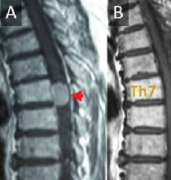

枕骨大孔区脑膜瘤案例。多年颈痛,竟是脑膜瘤在作怪德国一位57岁的女士,多年以来,一直饱受颈痛的折磨,近来,还出现了走路乏力,腿不听使唤且步...